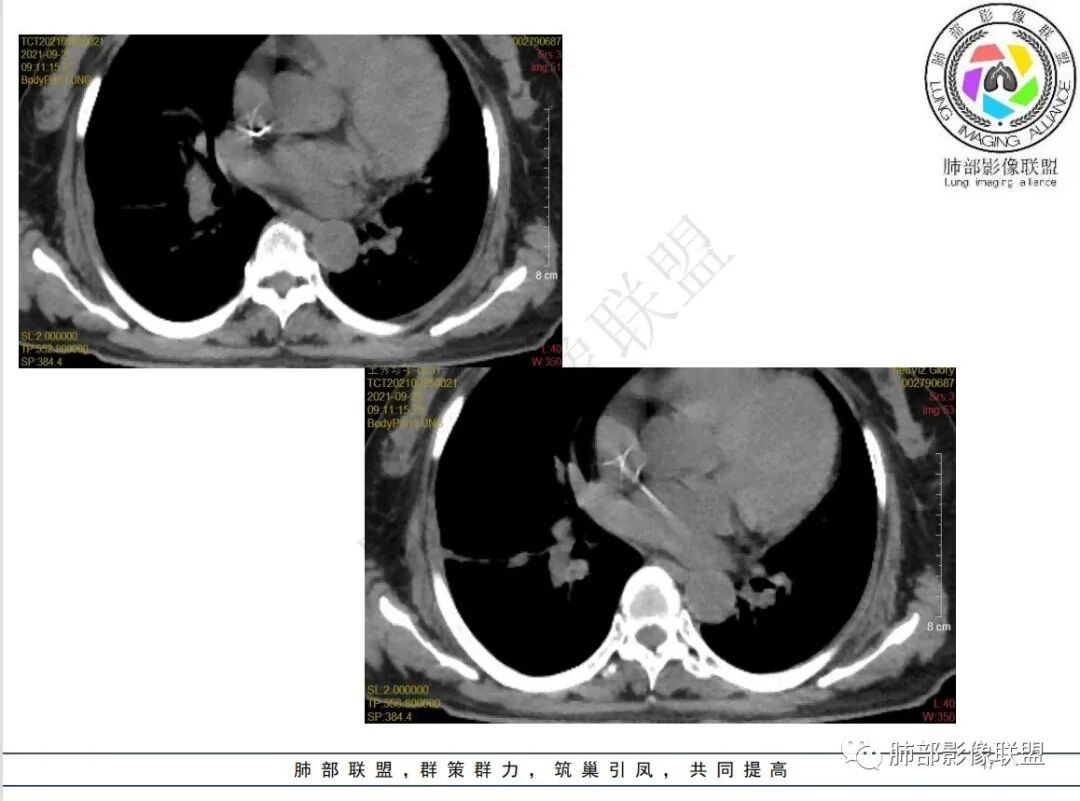

抗真菌治疗1月后复查

1.老年女性,既往白血病病史,并多次化疗,骨髓抑制明显。

2.此次急性起病,高热并咳嗽,偶有血性痰。

3.实验室培养出多种病原菌,并针对性覆盖多种抗感染药物,但肺部病灶却不断进展。

4.白血病化疗后,CT上出现多发结节,边缘可见晕征,病灶内可见多发坏死,右肺中叶肺动脉可见充盈缺损,右肺中叶可见融冰征,右肺中叶肺动脉侵犯栓塞伴右肺中叶肺梗死,可符合真菌感染。